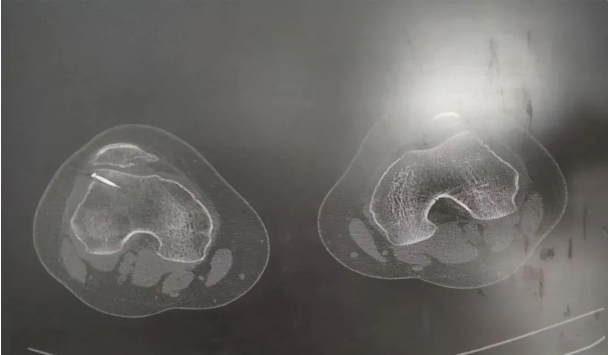

术前影像

一年前,郭师傅工作时不慎被重物砸伤双下肢,右膝关节较重,当时感觉右膝关节疼痛,肿胀,来我院就诊,经医生行CT检查后,以“右膝关节外伤、右股骨外侧髁骨骨折”,收住京东誉美医院骨科。